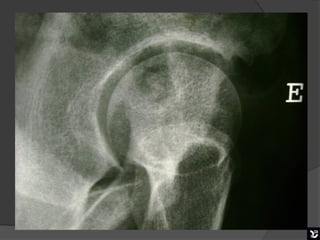

   Esta radiografia mostra bem uma boa mobilização na

incidência de Ducroquet. Podemos visualizar o colo

femoral bem alongado, trocanter menor visível em

perfil internamente.

PERFIL CIRÚRGICO DE ARCELIN

( CROSS TABLE)

   Posição supina com flexão do quadril contralateral e raio horizontal

e perpendicular ao colo femoral e ao filme, incidindo á face interna

da raiz da coxa que se quer avaliar em um ângulo de 45°.

Assim como na incidência de Ducroquet, o colo

femoral é visto em perfil permitindo uma boa

avaliação do colo e da porção anterior da transição

cabeça colo femoral.

Esta radiografia mostra bem uma boa mobilização na incidência de Ducroquet. Podemos visualizar o colo femoral bem alongado, trocanter menor visível em perfil internamente. Boa mobilização

PERFIL CIRÚRGICO DEARCELIN ( CROSS TABLE)  Posição supina com flexão do quadril contralateral e raio horizontal e perpendicular ao colo femoral e ao filme, incidindo á face interna da raiz da coxa que se quer avaliar em um ângulo de 45°.

Assim como naincidência de Ducroquet, o colo femoral é visto em perfil permitindo uma boa avaliação do colo e da porção anterior da transição cabeça colo femoral.